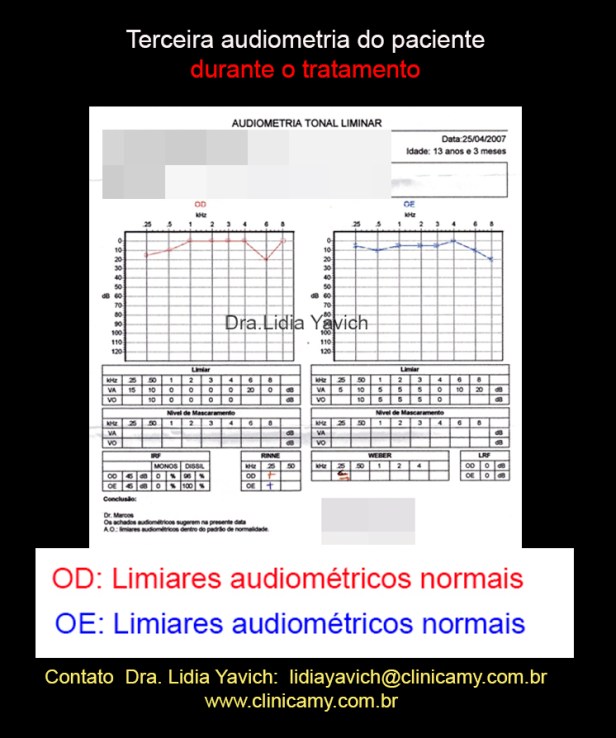

A terceira audiometria do paciente revela limiares normais no ouvido esquerdo e limiares normais no ouvido direito.

Comparação da primeira, segunda e terceira audiometria do paciente durante o tratamento.

Normalização dos limiares no ouvido direito e normalização dos limiares do ouvido esquerdo.